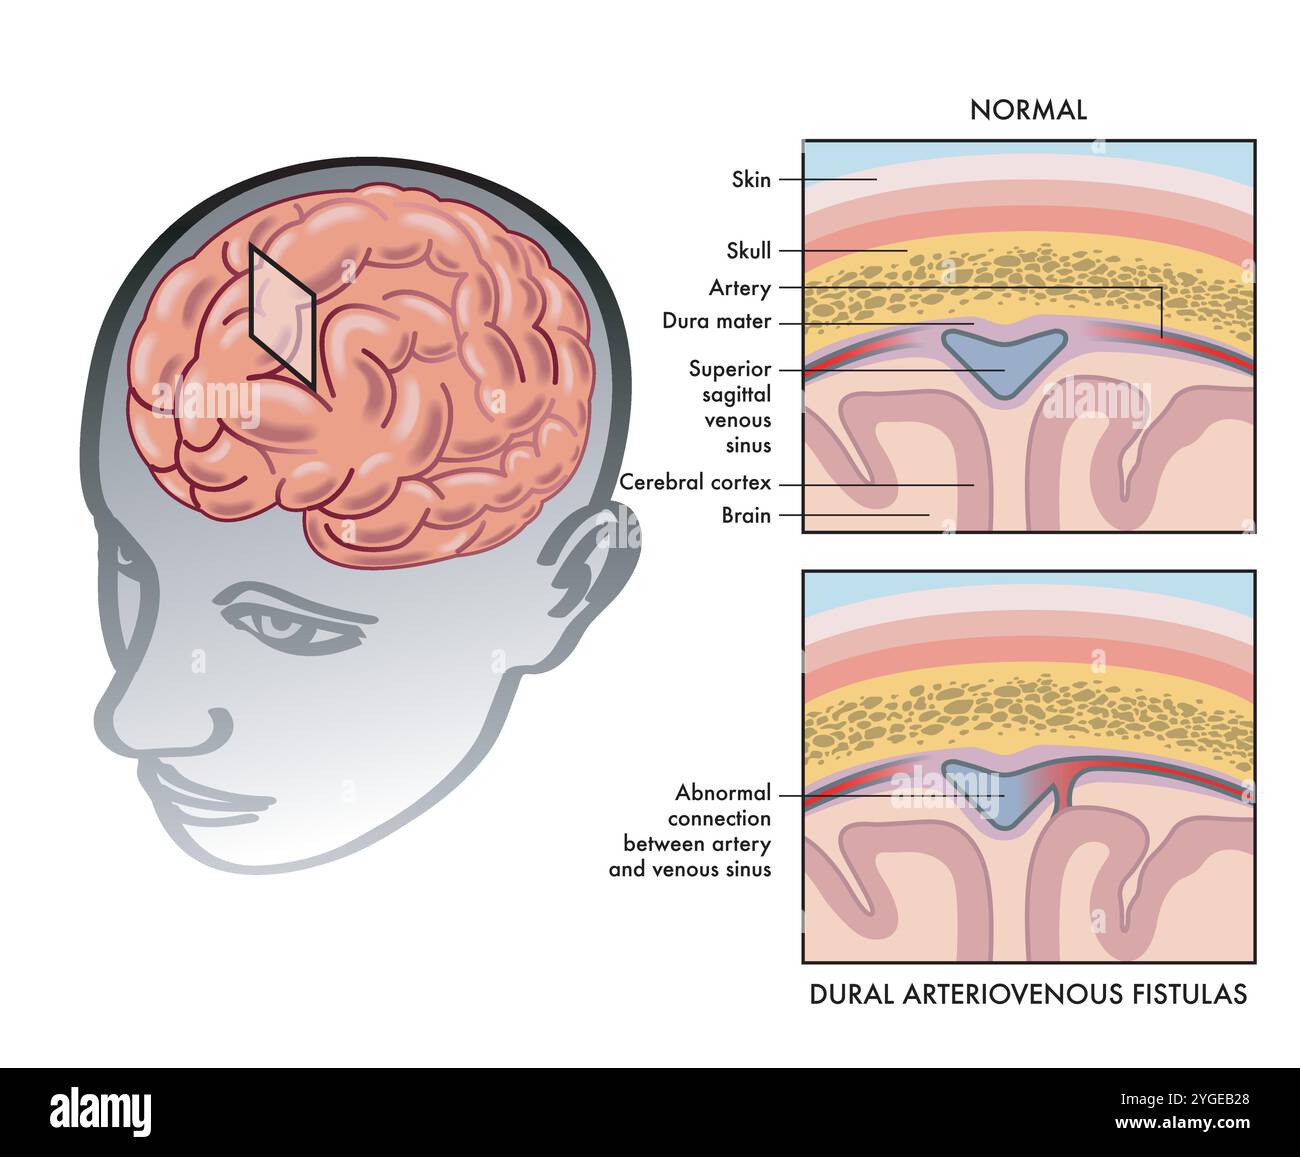

RF2YGEB28–Semplice illustrazione medica che mostra come una fistola arterovenosa durale si verifica nel cervello, con annotazioni.